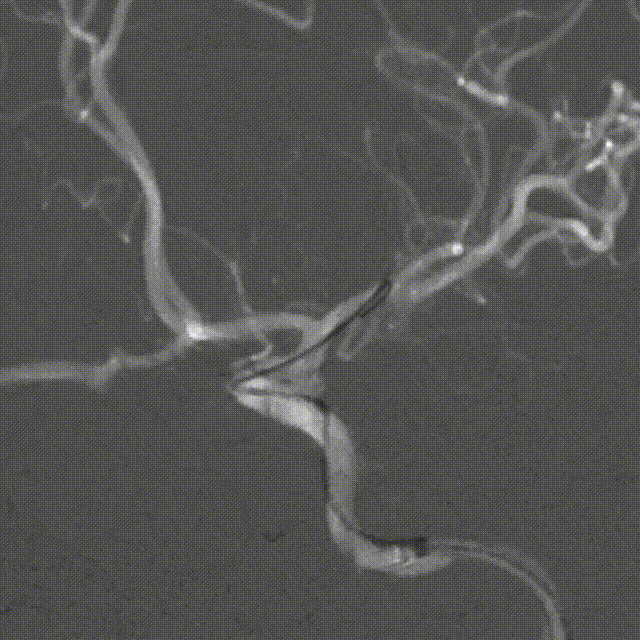

术后影像

➢术后工作位造影

病人术后:动脉瘤已完全栓塞,瘤体不显影,载瘤动脉通畅。